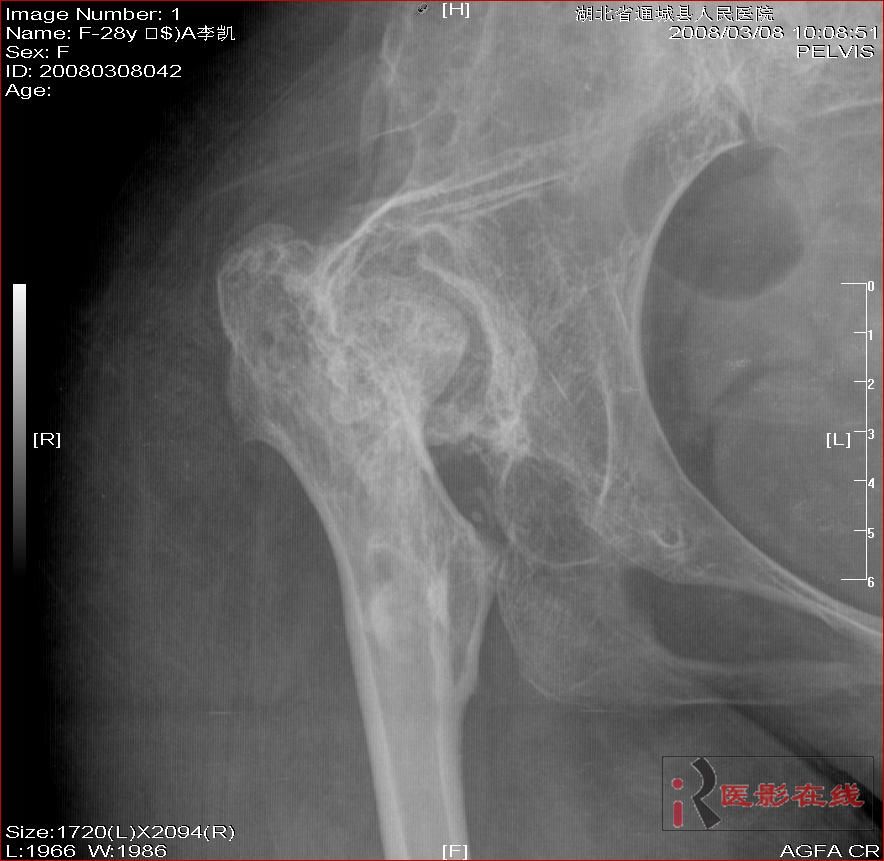

先天性双髋关节脱位自体骨关节再造

女 28岁 先天性髋关节脱位术后复查片(手术日期是2000年,数字化以前平片资料患者外带),现无其它不适,走路仍需双拐

2008年3月8日

双侧髋关节仍为脱位表现,假关节形成,部分已经强直,右股骨头碎裂,股骨干近端增粗。

结合手术史考虑:原地臼盖成形术后,髋关节退变,股骨头无菌性坏死,右股骨近端生长紊乱,骨质疏松。